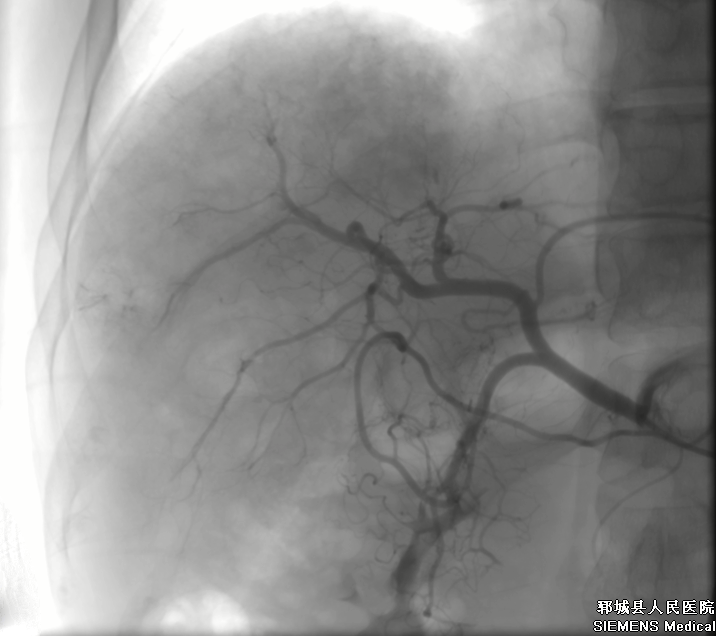

肝動(dòng)脈造影后超選插管到肝癌供血?jiǎng)用},并通過導(dǎo)管向供血?jiǎng)用}注射化療藥物和栓塞劑。

肝動(dòng)脈栓塞化療結(jié)束后再次造影:肝癌染色消失,栓塞腫瘤的供養(yǎng)血管,以盡量使腫瘤去血管化。